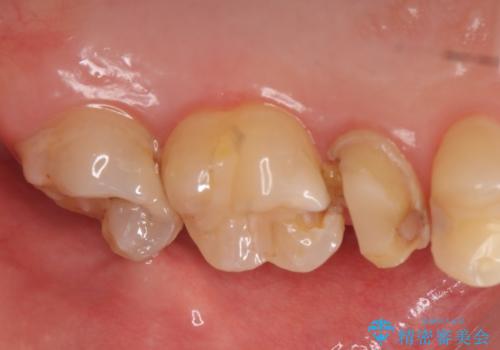

- 左上の歯が痛くてものが咬めないといらっしゃった方の症例です。

左上6は自発痛および持続痛を認めたため根管治療後、オールセラミッククラウンによる補綴を行いました。

左上7は冷水痛のみだったため、慎重に虫歯の除去を行い症状がないことを確認後、オールセラミッククラウンによる補綴を行いました。

左上5は再根管治療後、オールセラミッククラウンによる補綴を行いました。